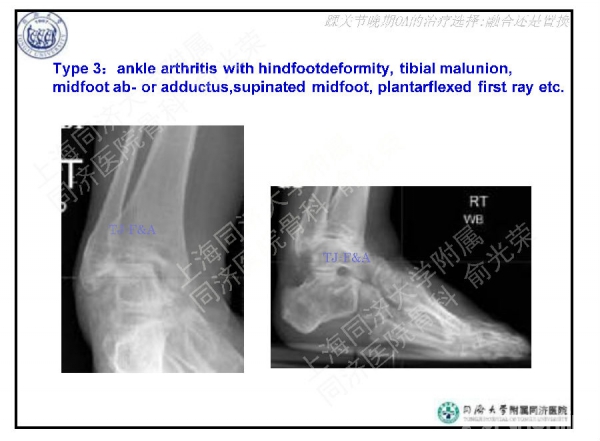

2016-01-14 文章来源:上海同济大学附属同济医院骨科 俞光荣 我要说